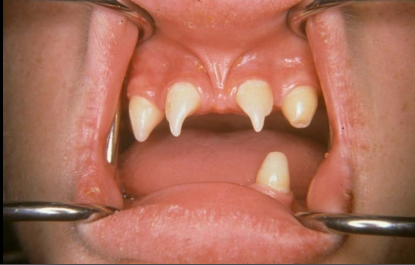

3 characteristics of hypohydrotic ectodermal dysplasia

• Hypohydrosis (abnormally diminished perspiration)

• Hypotrichosis

• Hypodontia with conical teeth